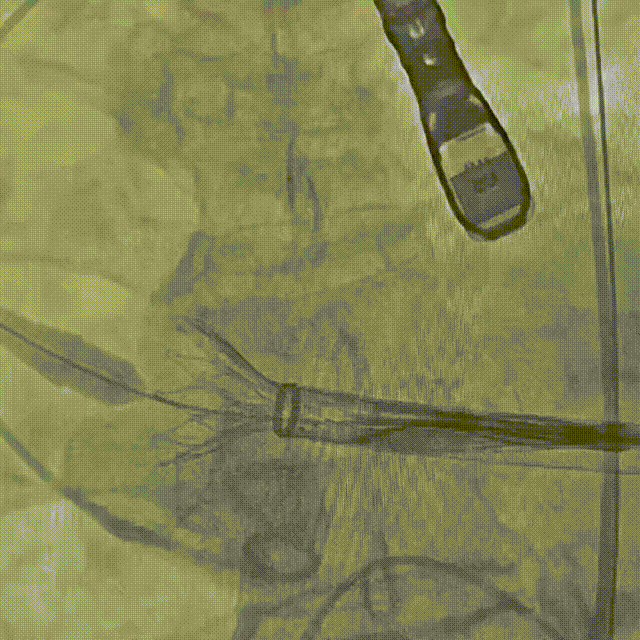

手术操作:该患者流出道敞口型,流出道无锚定力,瓣上空间扩张,需充分利用瓣环锚定;同时瓣膜横位心验证,术中需充分利用瓣膜全可回收功能,评估瓣膜稳定性

辅入路猪尾根部造影(右窦居中)

瓣膜初始定位

瓣膜开花后造影确认位置

起搏下释放瓣膜至全展开

全展开后造影评估

瓣膜打平造影评估

瓣膜位置可,形态可

脱钩后造影,瓣膜无位移,形态可

弓部剪影,无瓣周漏,升主无损伤